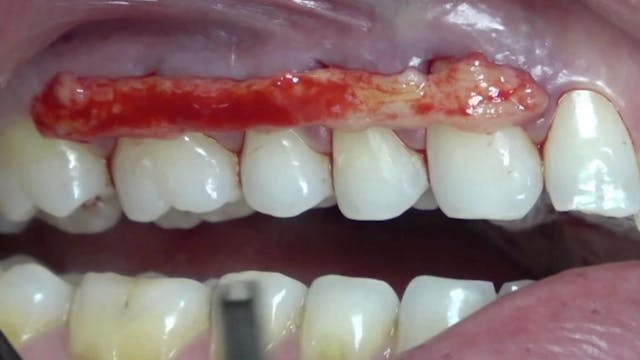

This clinical video presents a comprehensive root coverage procedure aimed at addressing gingival recessions affecting two lower teeth. The treatment strategy involves employing a tunneling technique combined with connective tissue grafting harvested from the palate.

The video begins with a detailed examination of the gingival recessions, assessing their extent and severity. Subsequently, the surgical approach is outlined, focusing on the tunneling technique to preserve papillary integrity and enhance aesthetic outcomes. The use of a palatal connective tissue graft is highlighted as a reliable method for augmenting soft tissue thickness and achieving predictable root coverage.

During the surgical procedure, meticulous attention is paid to flap elevation, root planing, and precise placement of the connective tissue graft within the tunnel created beneath the gingival margin. The importance of proper suturing techniques to stabilize the graft and optimize wound healing is emphasized.